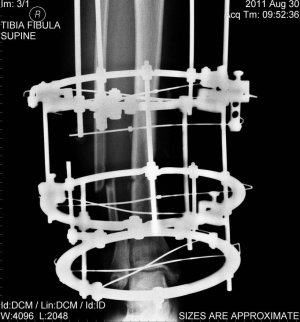

Возник вопрос об упражнениях для реабилитации после перелома голени и пятки (реабилитолог поликлиники сейчас в отпуске). Перелом произошел 3 месяца назад, наложение аппарата Илизарова осуществлено на неделю позже.

На данный момент могу поднимать стопу на 1 см максимум со слабым усилием, также создавать небольшое на опускание стопы. Пальцы но могу опускать (вжимать) нормально, но принципиально не могу поднимать (разжимать). Опухлость верхней части стопы держится все 3 месяца.